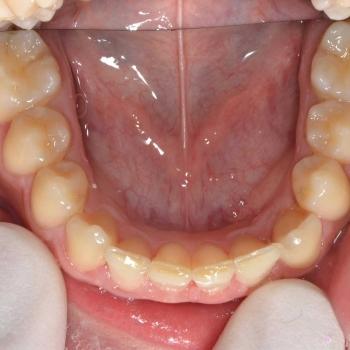

Ádám és édesanyja fogorvosuk javaslatára kerestek fel a felső állcsontban rekedt maradó szemfogak sorbaállításának kérésével. A panoráma röntgenfelvétel elemzése alapján egyértelművé vált, hogy a maradó szemfogak hibás tengelyállása okozta a tej szemfogak perzisztenciáját és a maradó szemfogak előtörésének a hiányát. A szemfogak 30 és 45 fokos dőlésének klinikai képet tovább árnyalták egyéb fogszabályozási eltérések is, mint például a mélyharapás, a nagymetszők közötti rés, illetve jobb oldali második nagyőrlők közötti fordított keresztharapás.

A probléma súlyosságát figyelembe véve, Ádám nagyon bölcsen az önligírozó fém fogszabályozó mellett döntött, melyet bite turbo harapásemelővel és különböző intermaxilláris gumihúzásokkal egészítettünk ki. Az önligírozó fogszabályozó ellenére a kezelés ideje igen hosszú volt. Ennek oka, hogy a szemfogak szájsebészeti feltárása közben derült fény a levontatantó fogak dőlésén kívüli 100-160 fokos tengely körüli elcsavarodására is.

Ádám kitartásának köszönhetően a kezelés végére minden maradó fog a helyére került és egy esztétikailag és funkcionálisan is tökéletes harapást kaptunk.